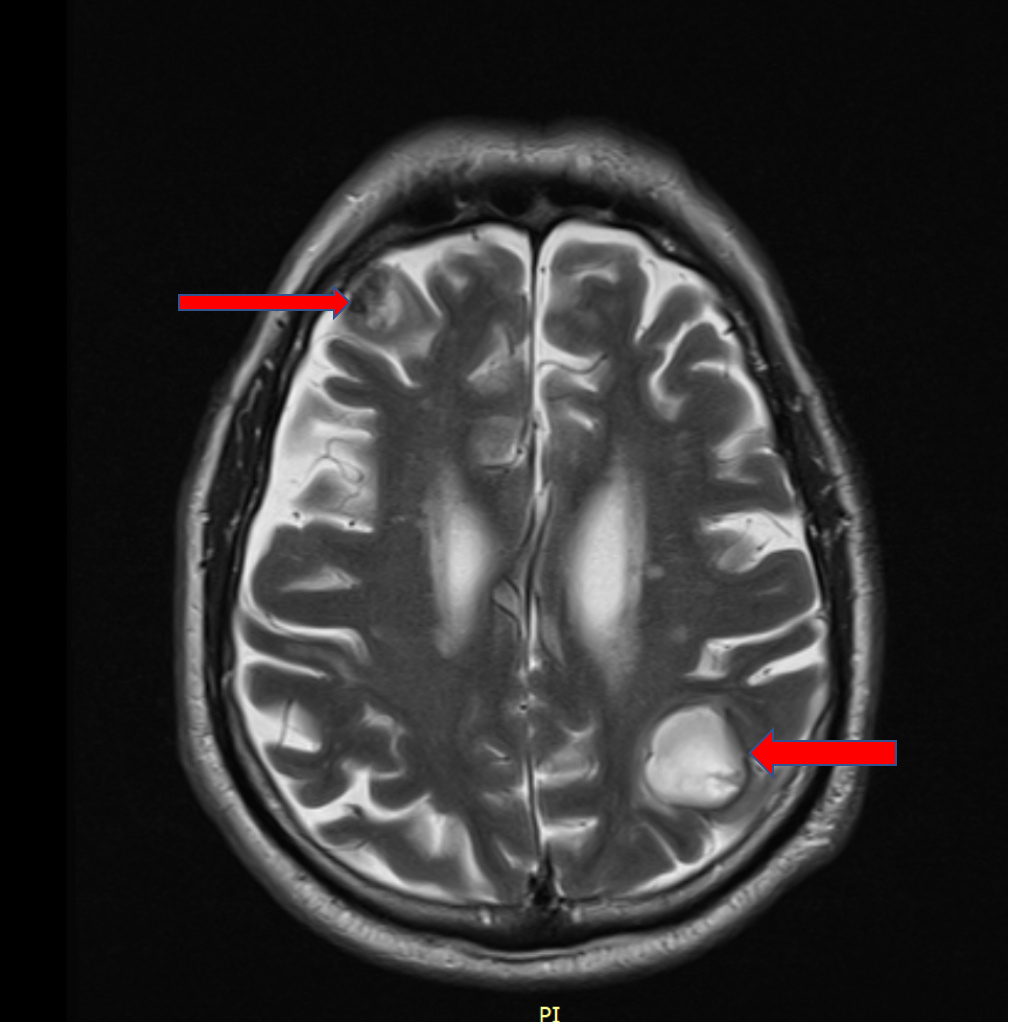

🧠 В первую очередь выполнено МРТ головного мозга и сразу выявлено значимое поражение в виде множественных очагов с кровоизлияниями.

Стрелочками выделены новообразования головного мозга больших размеров

➡️ Больше всего картина МРТ соответствовала метастатическому поражению головного мозга.